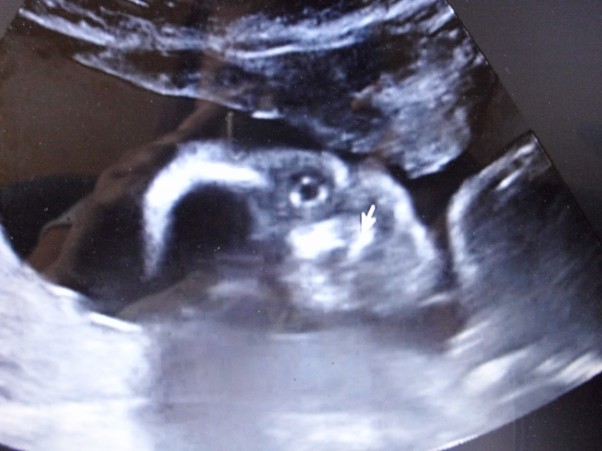

Kilka dni temu byliśmy Z tatusiem Cię podejrzeć nasz kochany Okruszku i okazało się że jesteś dziewczynką :) teraz w końcu będziemy mogli rozpocząć przygotowywać się żeby wszystko było gotowe gdy przyjdziesz na świat...